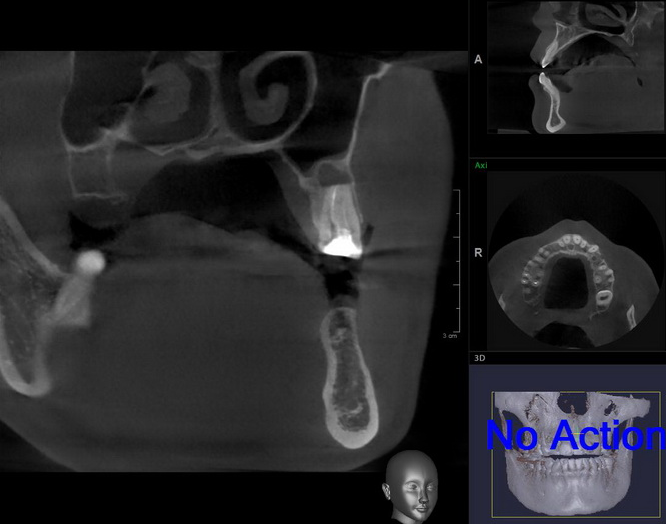

Для примера, давайте рассмотрим вот этот снимок:

Возможна ли имплантация в области левого верхнего премоляра? Вполне. Зуб и гранулему можно удалить, сделать синуслифтинг, вопрос со стабилизацией импланта решить по ходу операции. Остается только один вопрос:

— зачем усложнять?

Другой вариант лечения: удаление зуба, аугментация лунки, через полтора месяца можно приступать к имплантации. Без всяких синуслифтингов и проблем, связанных со стабилизацией импланта. Атрофия альвеолярного гребня? Эта проблема решается на этапе аугментации лунки.

Продолжу рассказ о клиническом случае, который начал со снимка выше.

Итак, у пациентки был выбор: либо немедленная имплантация с синуслифтингом и неясным прогнозом, либо чуть более длительное лечение, но без синуслифтинга и геморроя со стабилизацией. И, поскольку ипотеку я уже давно отдал, мы пошли именно по второму пути.